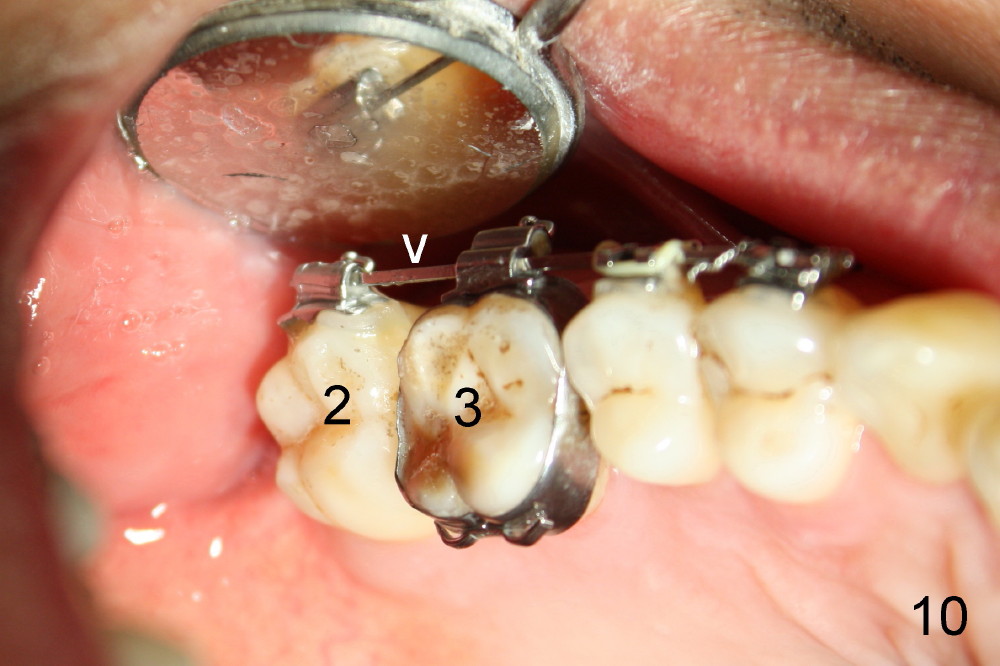

In 7 months, the right molar occlusion changes to Class I with normal overjet (Fig.8 mirror view). Class I posterior occlusion correction is evidenced by a gap between the teeth #30 and 31 (Fig.9 arrowheads) due to elastic retraction. There is no tension (bending) of wire between the teeth #2 and 3 in the final stage (Fig.10 arrowhead, as compared to Fig.7). A porcelain crown is subsequently cemented to the implant/abutment complex with occlusal equilibrium (Fig.11(mirror image) C). The remaining brackets and band are removed. Power chains in Fig.11 (arrowhead) were used to correct the rotation of the tooth #2 (Fig.10, bracket in the tooth was not well placed).